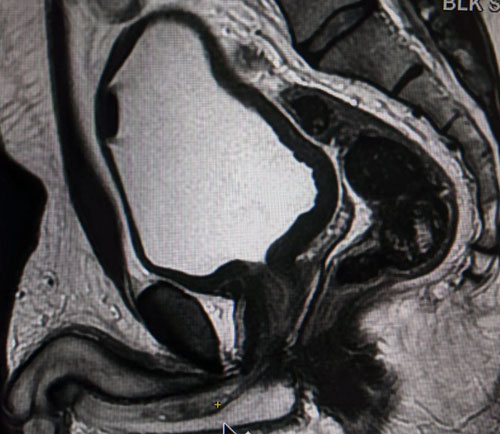

A 47-year-old male presented with two months history of obstructive urinary symptoms and intermittent per urethral bleed. Ultrasound revealed mild prostatomegaly with significant post-void residual urine. Uroflowmetry was suggestive of decrease maximum flow and stricture pattern. Retrograde urethrogram confirmed stricture in mid-bulbar urethra and filling defect proximal to it with possibility of either radiolucent calculus or soft tissue mass (Figure 1). Magnetic resonance imaging (MRI) reported it as altered intensity polypoidal lesion in bulbar urethra suggestive of urethral malignancy (Figure 2). Cystoscopy revealed mid-bulbar stricture and polypoidal lesion proximal to it with overlying calcified material imitating as malignancy (Figure 3A and Figure 3B). Optical internal urethrotomy and transurethral resection of mass were done with transurethral resection loop without cutting current followed by optical internal urethrotomy for another stricture proximal to it with no skip lesion elsewhere. Histopathology confirmed the lesion as NA with positive immunohistochemistry for CK7, PAX 2, and negative for p63. Foley catheter was removed after five days and the patient is asymptomatic till date.

Figure 2: MRI pelvis showing lesion (yellow asterisk) in midbulbar urethra.